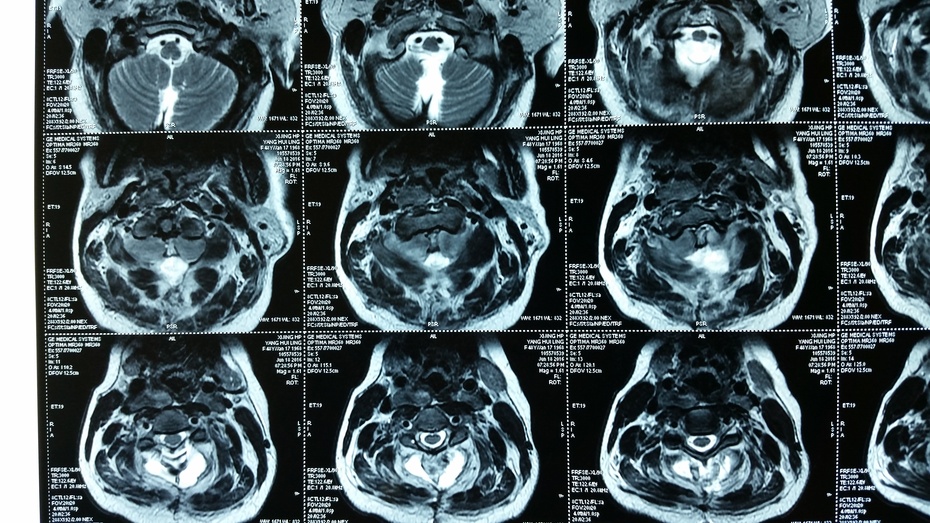

颈1椎管内神经鞘瘤病例分享一例